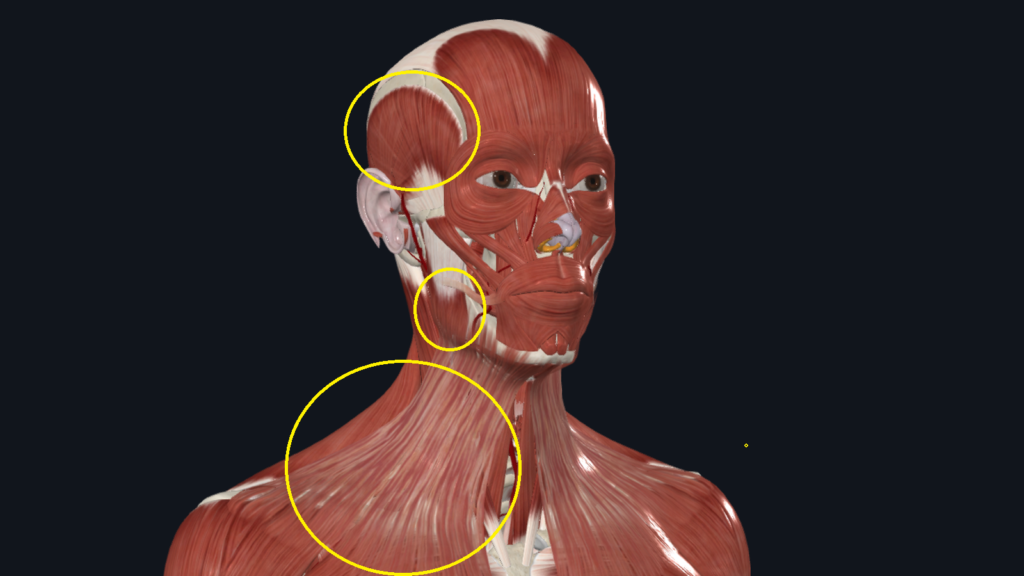

対策④ マグネシウムオイルを塗る

マグネシウムは皮膚から吸収されやすく、 筋肉の緊張を和らげる作用があります。

特におすすめの部位は、

- こめかみ(側頭筋)

- エラ部分(咬筋)

- 首の前(斜角筋・胸鎖乳突筋・広頚筋)

- デコルテ(小胸筋)

サプリよりも、オイルとして直接塗布する方が実感しやすいです。

※解剖学アプリを使用し、筆者が作成した画像です